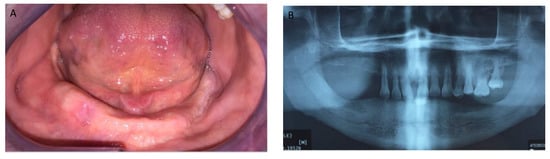

Figure 1, Figure 2, Figure 3, Figure 4, Figure 5, Figure 6 and Figure 7 show the progress of treatment in one of the patients of the test group. In Figure 3 reduction of the medullar space is visible, that may create a chronic ischemic area susceptible to necrosis.

Figure 2.

Pre-operative orthopantomography of the same MRONJ patient showing bilateral defect; (A) shows the panoramic view; (B) shows more detail of the right side of the mandible.

Figure 3.

Pre-operative CBCT of the MRONJ patient, showing a reduction in the medullar space.